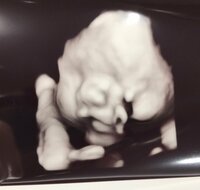

この日、「妊婦健診でした」と述べ、「恐れていた妊娠糖尿病の検査はクリアしててホッとしたー」と安堵した様子で報告。「今回の3Dエコー写真しっかりと顔が写っててすごい」とつづりエコー写真を公開した。

続けて、「エコー写真だけを見ると、ヒロさんに似てる気がする」と明かし、「この時点で愛おしい~」と嬉しそうにコメント。「写真を見ると、本物に会える日がより楽しみだなぁ」と期待を寄せた。